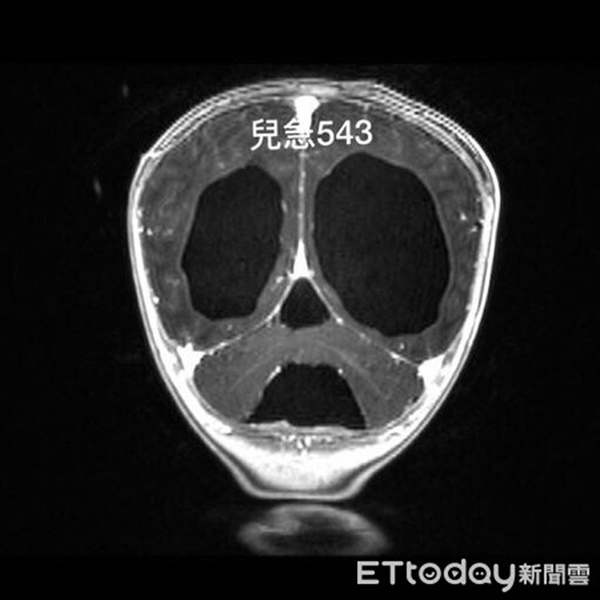

Tiến hành chụp cộng hưởng từ (MRI), phát hiện bệnh nhi mắc bệnh não úng thủy nghiêm trọng. Ban đầu, bác sĩ hoài nghi có khối u trong não bệnh nhi, nhưng sau đó xác định là não úng thủy bẩm sinh. Sau khi tiến hành phẫu thuật chọc hút dịch não, tình trạng của bệnh nhi cơ bản đã ổn định.

BS Ngô Xương Đằng chia sẻ: "Khi bệnh nhi được đưa vào phòng cấp cứu, vòng đầu của bệnh nhi gia tăng thấy rõ, điều này chứng minh tình trạng của bệnh nhi đã kéo dài hơn 1 tháng. Tuy bệnh nhi đã được chọc hút dịch não tủy, nhưng dịch não tủy đã gia tăng áp suất lên não bộ trong thời gian dài, e là sẽ ảnh hưởng đến chức năng vận động và sự phát triển của hệ thần kinh. Di chứng để lại có lẽ là chậm phát triển về ngôn ngữ, bệnh nhi cần phải tái khám và theo dõi sát sao về lâu dài".